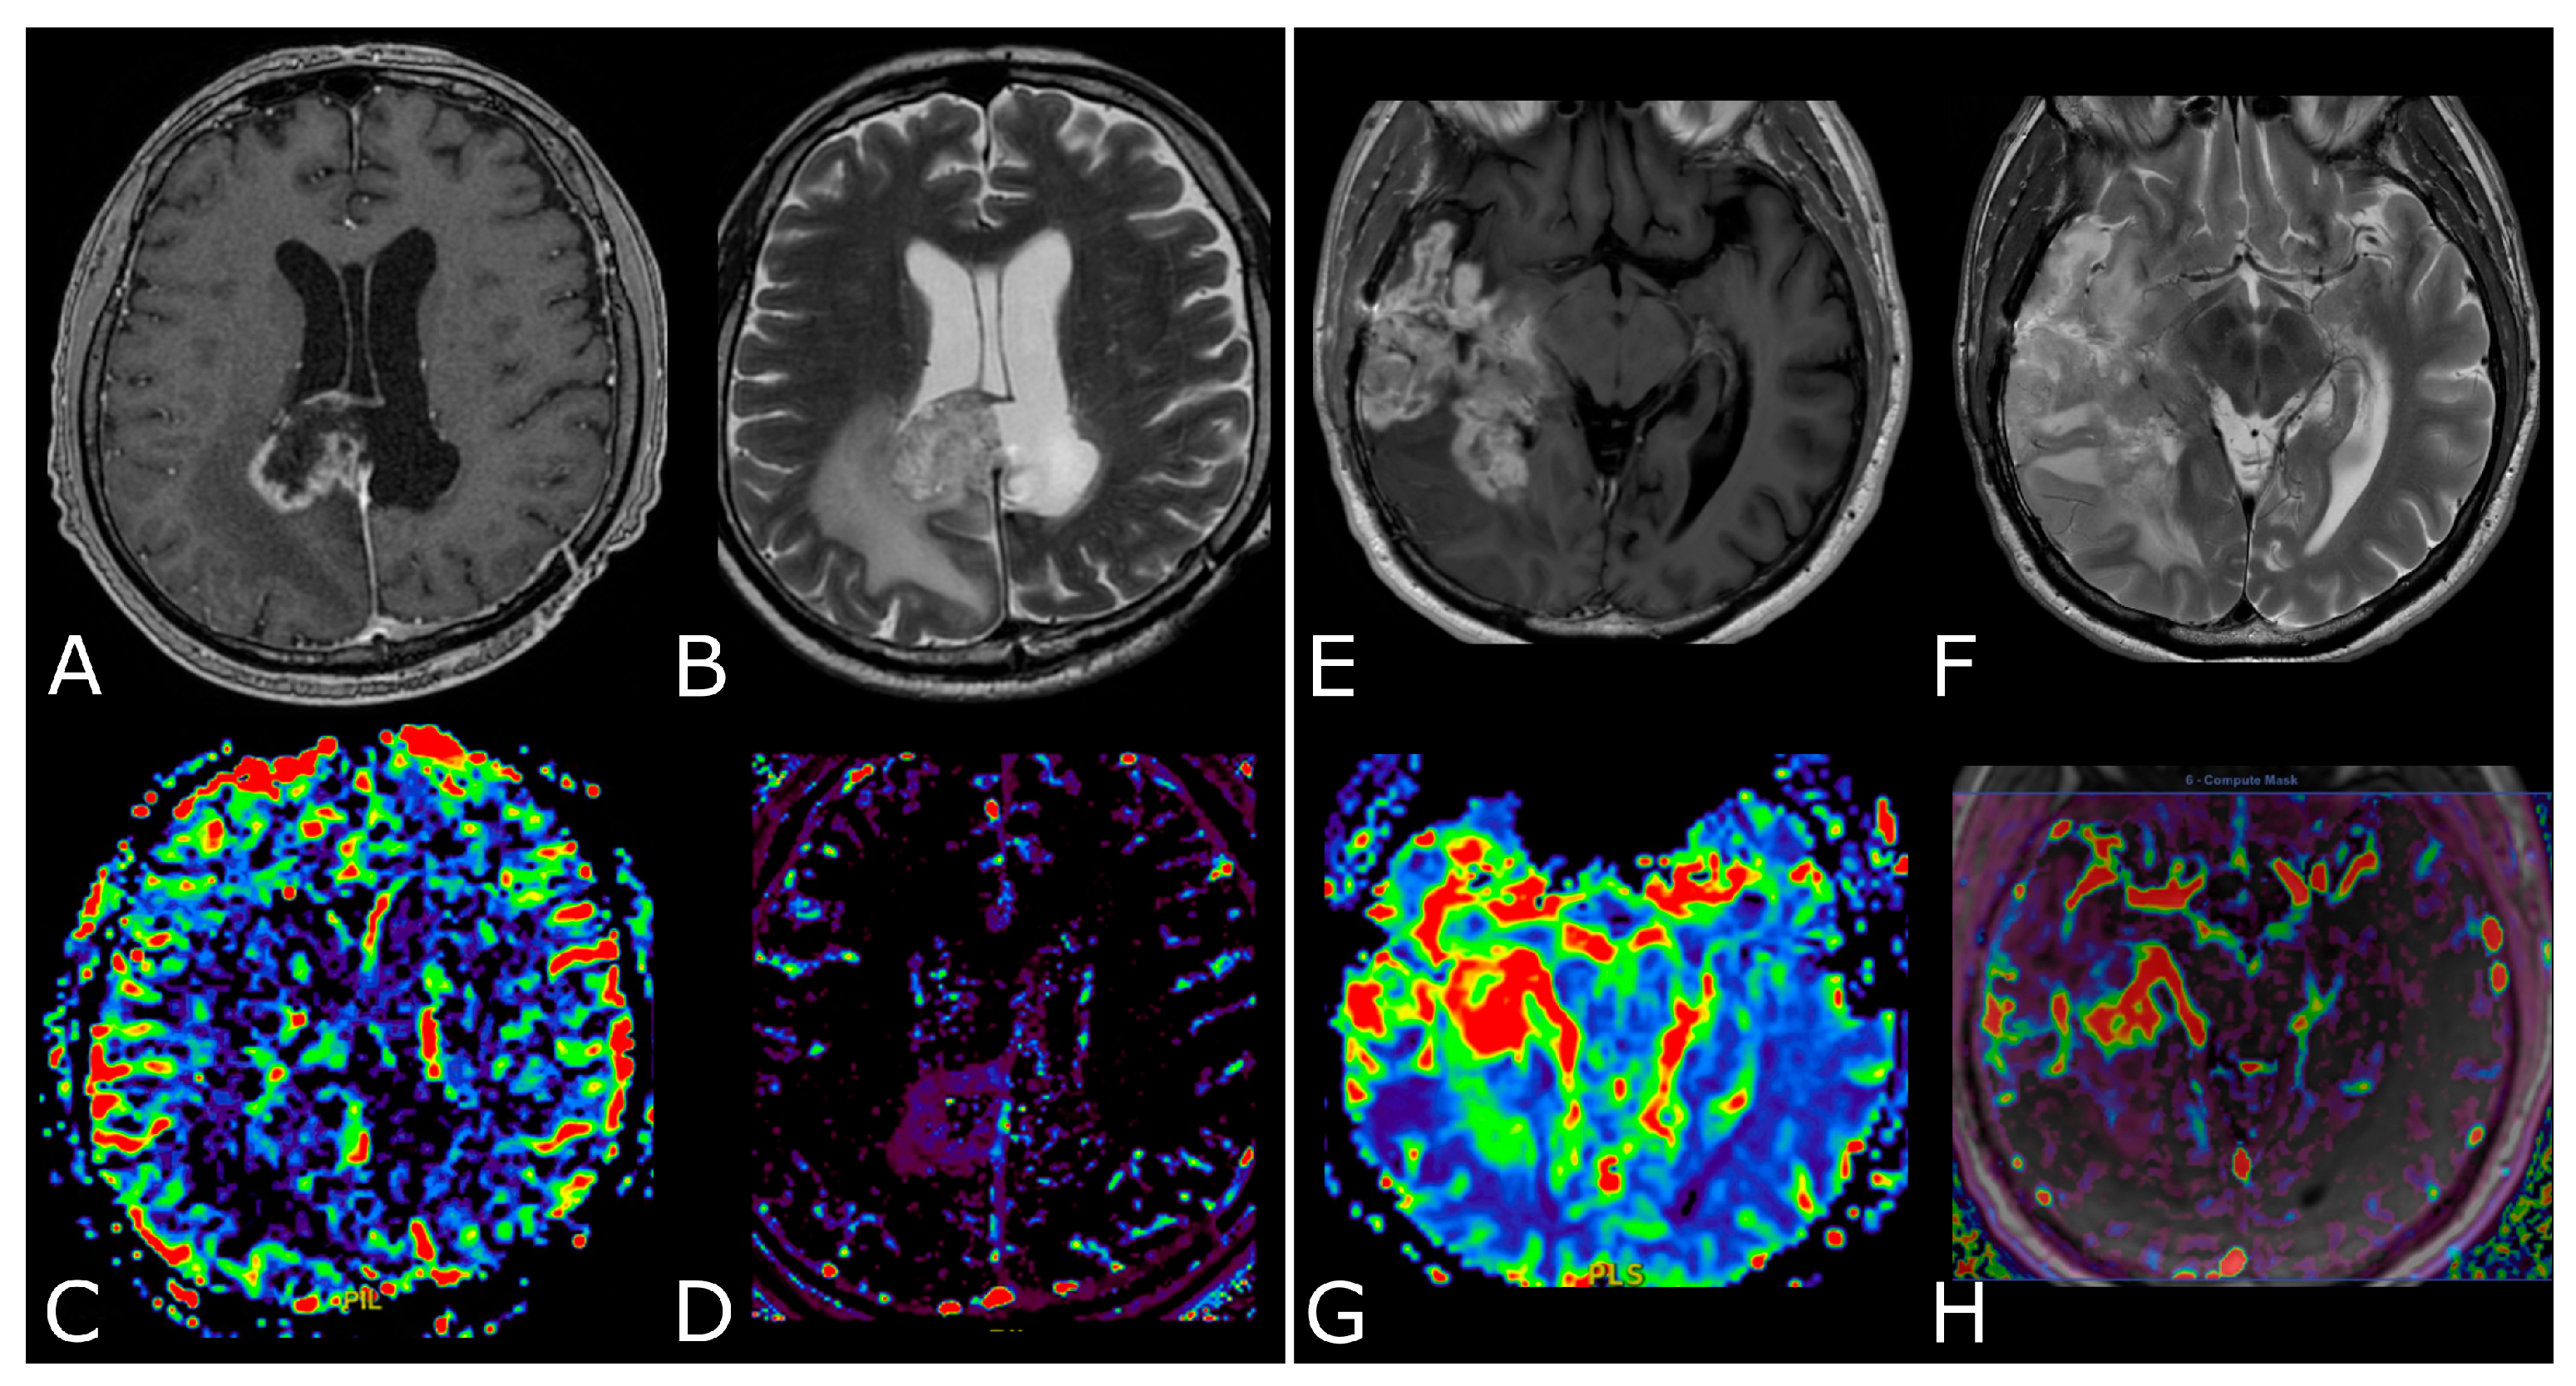

3. MR Perfusion

3.1. Overview and Techniques

3.2. Clinical Applications

3.2.1. Differentiating HGG from LGG and Clinical Prognosis

3.2.2. Differentiating Tumors on the Basis of the Genetic Profiles

3.2.3. Differentiating Recurrent Tumor from Pseudoprogression and Radiation Necrosis and Be Aware of Pseudoresponse